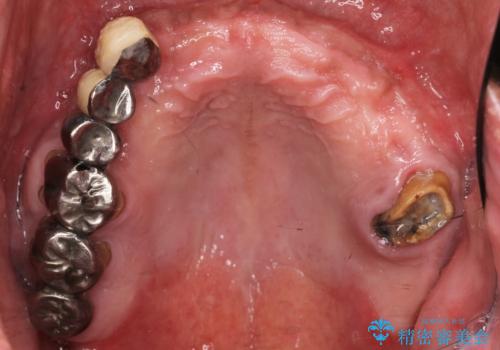

- 歯がないまま放置しており咬めないことを主訴に来院された患者様です。

仕事が忙しくなかなか自分のことに気が回らなかったそうですが、どんどん歯が抜け落ちて「もう限界だ!」と思い受診を決断したとのことでした。

精査したところ、全顎的な重度の歯周病により上顎前歯はすべて欠損していました。

禁煙指導と歯周病治療後、インプラント治療を行うことにしました。